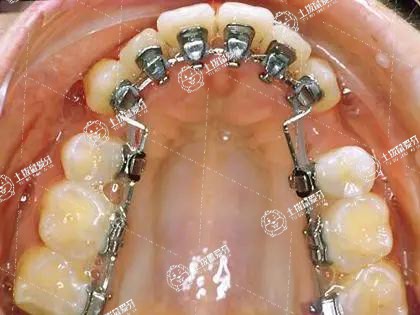

隱形矯正分為無托槽隱形矯正和舌側隱形矯正,其中舌側隱形矯正的優(yōu)勢如下:

2、舌側粘接托槽進行矯正,即美觀又舒適,可以完全做到隱形矯正;

舌側矯治還可以大大降低牙齒的齲齒率,減少矯治后復發(fā)的可能性,避免唇部矯治器會造成的唇部損傷。另外,由于舌側矯正技術增強了對后牙阻力的控制,也能更有效地控制牙齒的移動。